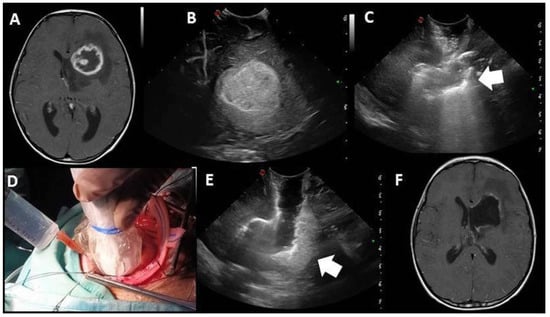

| EOR | Collapsed surgical cavity |

|

| EOR | Open ventricle |

| EOR | Artifacts |